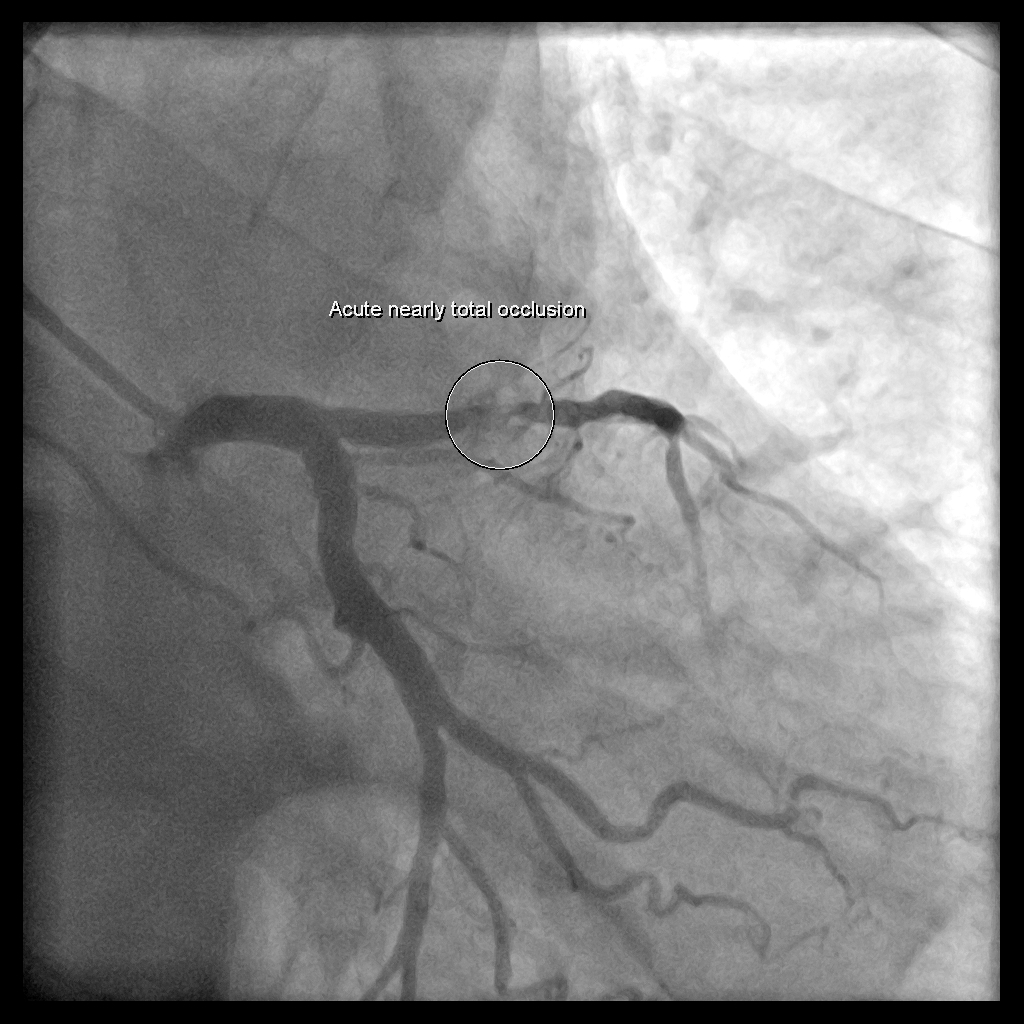

住院上去,當天早上就做了CAG: CAG報告➜ LAD: pLAD critical lesion, plaque rupture with thrombus formation and 95% stenosis, impaired TIMI flow; dLAD discrete lesion with 70% stenosis